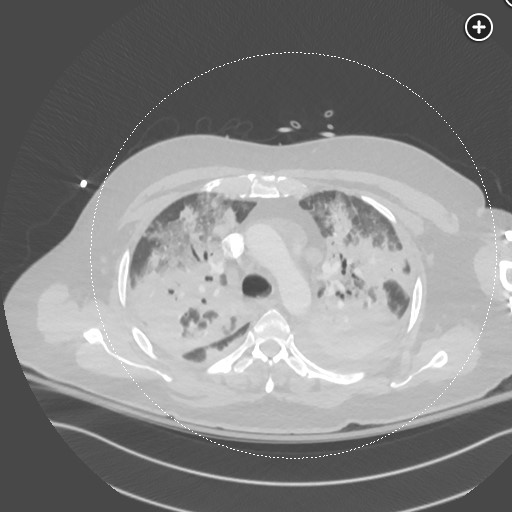

DAH CT finding includes consolidation or ground glass opacities related: DAH diffuse alveolar hemorrhage tags: #literature #pulmonology ground glass: consolidations: 1 Links to this note DAH diffuse alveolar hemorrhage DAH CT finding includes consolidation or ground glass opacities Footnotes SEEK Questionnaires ↩